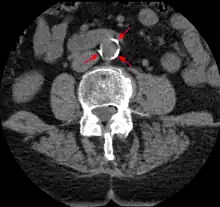

The calcification deposits,[70] after they have become sufficiently advanced, are partially visible on coronary artery computed tomography or electron beam tomography (EBT) as rings of increased radiographic density, forming halos around the outer edges of the atheromatous plaques, within the artery wall. On CT, >130 units on the Hounsfield scale (some argue for 90 units) has been the radiographic density usually accepted as clearly representing tissue calcification within arteries. These deposits demonstrate unequivocal evidence of the disease, relatively advanced, even though the lumen of the artery is often still normal by angiography.

Examples of anatomical detection methods include coronary calcium scoring by CT, carotid IMT (intimal media thickness) measurement by ultrasound, and intravascular ultrasound (IVUS). Examples of physiologic measurement methods include lipoprotein subclass analysis, HbA1c, hs-CRP, and homocysteine. Both anatomic and physiologic methods allow early detection before symptoms show up, disease staging, and tracking of disease progression. Anatomic methods are more expensive and some of them are invasive in nature, such as IVUS. On the other hand, physiologic methods are often less expensive and safer. But they do not quantify the current state of the disease or directly track progression. In recent years, developments in nuclear imaging techniques such as PET and SPECT have provided ways of estimating the severity of atherosclerotic plaques.[78]